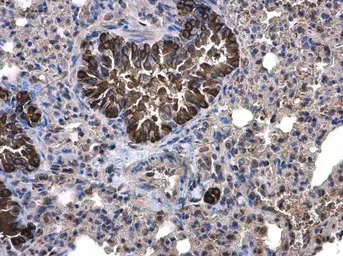

Anti-Calpain 1 antibody [N3C2], Internal used in IHC (Paraffin sections) (IHC-P). GTX102340

GTX102340 IHC-P Image

Calpain 1 antibody [N3C2], Internal detects Calpain 1 protein at cytoplasm on mouse lung by immunohistochemical analysis.

Sample: Paraffin-embedded mouse lung.

Calpain 1 antibody [N3C2], Internal (GTX102340) diluted at 1:500.

Antigen Retrieval: Trilogy™ (EDTA based, pH 8.0) buffer, 15min